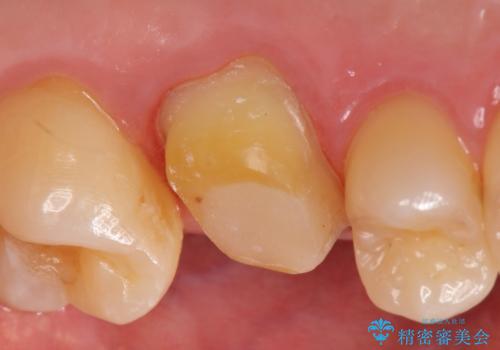

検査の結果歯の神経が死んでいたため根管治療を施し、症状が治まったのを確認後オールセラミッククラウンによる補綴を行いました。

今回用いたオールセラミッククラウンはジルコニアフレームという白い素材の上にセラミックを盛っているため、審美性が非常に高いのが特徴です。

また、ジルコニアは人工ダイヤモンドの材料にも使われているほど高い強度を持っており、そのためオールセラミッククラウンは審美性だけでなく、奥歯やブリッジの補綴も可能とするクラウンです。